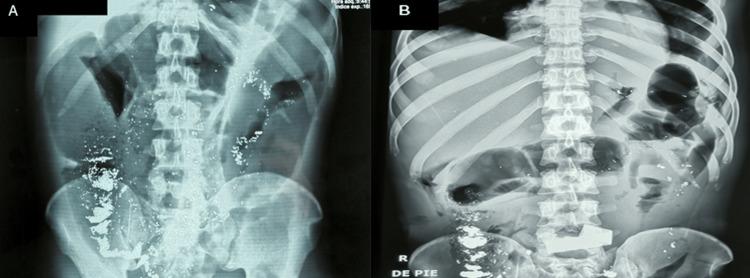

Elemental mercury ingestion caused by folk practices is rare and usually harmless. Nevertheless, some complications related to mercury ingestion have been reported such as appendicitis related to mercury sequestration and poisoning leading to systemic toxicity. Patients usually present with nausea, vomiting, and abdominal tenderness. Mercury sequestration in the appendix depends on its anatomy and mercury physical properties, both of which may lead to appendicitis, resulting in subsequent peritonitis leading to multiple and severe surgical complications. A 26-year-old Peruvian man complaining of vomiting and abdominal pain after ingestion of elemental mercury as part of a folk practice presented to the emergency department. Physical exam was remarkable for rigid abdomen and diffuse rebound sign. A clinical diagnosis of peritonitis was made. The patient was taken to the operating room where an open appendectomy and peritoneal lavage were performed. On gross inspection, a silver foreign body within the perforated appendix was seen by the surgical team. The patient developed multiple surgical complications leading to multiple organ failure and death. Clinicians should be aware that mercury ingestion is usually benign. However, severe complications may develop. Early surgical and medical intervention should be initiated promptly to achieve better outcomes. We present the first case of peritonitis due to appendicitis related to mercury sequestration in the appendix.

民间习俗导致的元素汞摄入情况罕见,通常无害。然而,已有一些与汞摄入相关的并发症报道,如与汞潴留相关的阑尾炎以及导致全身毒性的中毒。患者通常表现为恶心、呕吐和腹部压痛。阑尾中的汞潴留取决于其解剖结构和汞的物理特性,这两者都可能导致阑尾炎,进而引发腹膜炎,导致多种严重的手术并发症。一名26岁的秘鲁男子因参与民间习俗摄入元素汞后出现呕吐和腹痛,前往急诊科就诊。体格检查发现腹部僵硬和弥漫性反跳痛。临床诊断为腹膜炎。患者被送往手术室,进行了开放式阑尾切除术和腹腔灌洗。在大体检查中,手术团队在穿孔的阑尾内发现了一个银色异物。患者出现了多种手术并发症,导致多器官功能衰竭和死亡。临床医生应意识到汞摄入通常是良性的。然而,可能会出现严重并发症。应及时启动早期手术和医疗干预以获得更好的结果。我们报告了首例因阑尾汞潴留导致阑尾炎进而引发腹膜炎的病例。